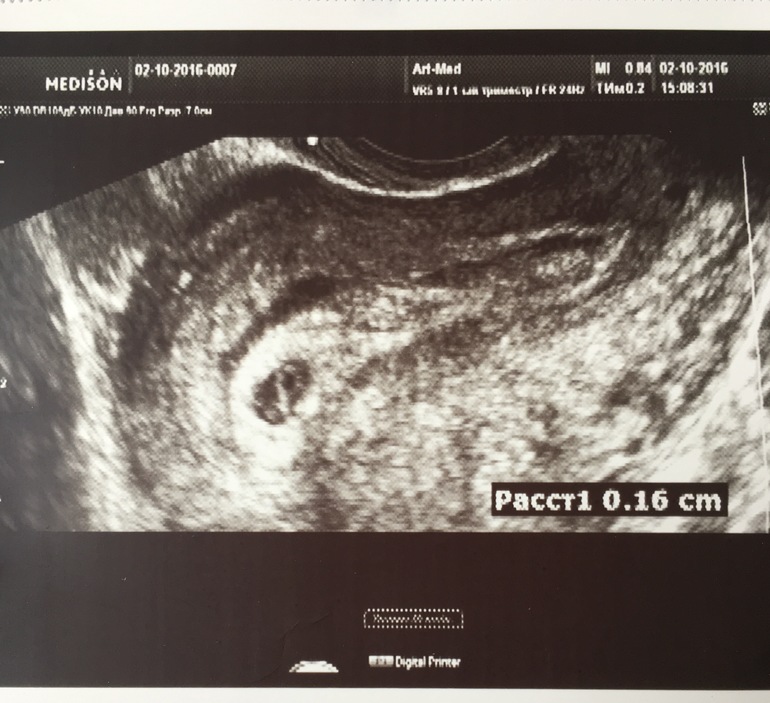

Девочки, вчера была на УЗИ. Результат совсем не такой, с каким выписали из больницы (пя 14 мм). Врач сказала, что я тяну на 5 недель, а у меня уже 8-я идёт, понятное дело, что была поздняя овуляция. Сказала сдать ХГЧ в динамики и с результатами к ней в субботу, боится, что может быть не развивающаяся. Ещё ей не понравилось, что полость пя-не совсем однородная. Под кат.все результаты включая сегодняшний ХГЧ(предыдущий сдавала 22 сентября был 2131) Посмотрите, пожалуйста! Мне очень нужны ваши мнения🙏🏻😞

зайка, неделю назад для твоего срока оно было идеально

Сейчас 6,6 мм это очень очень мало

И оно могло сдуться😔